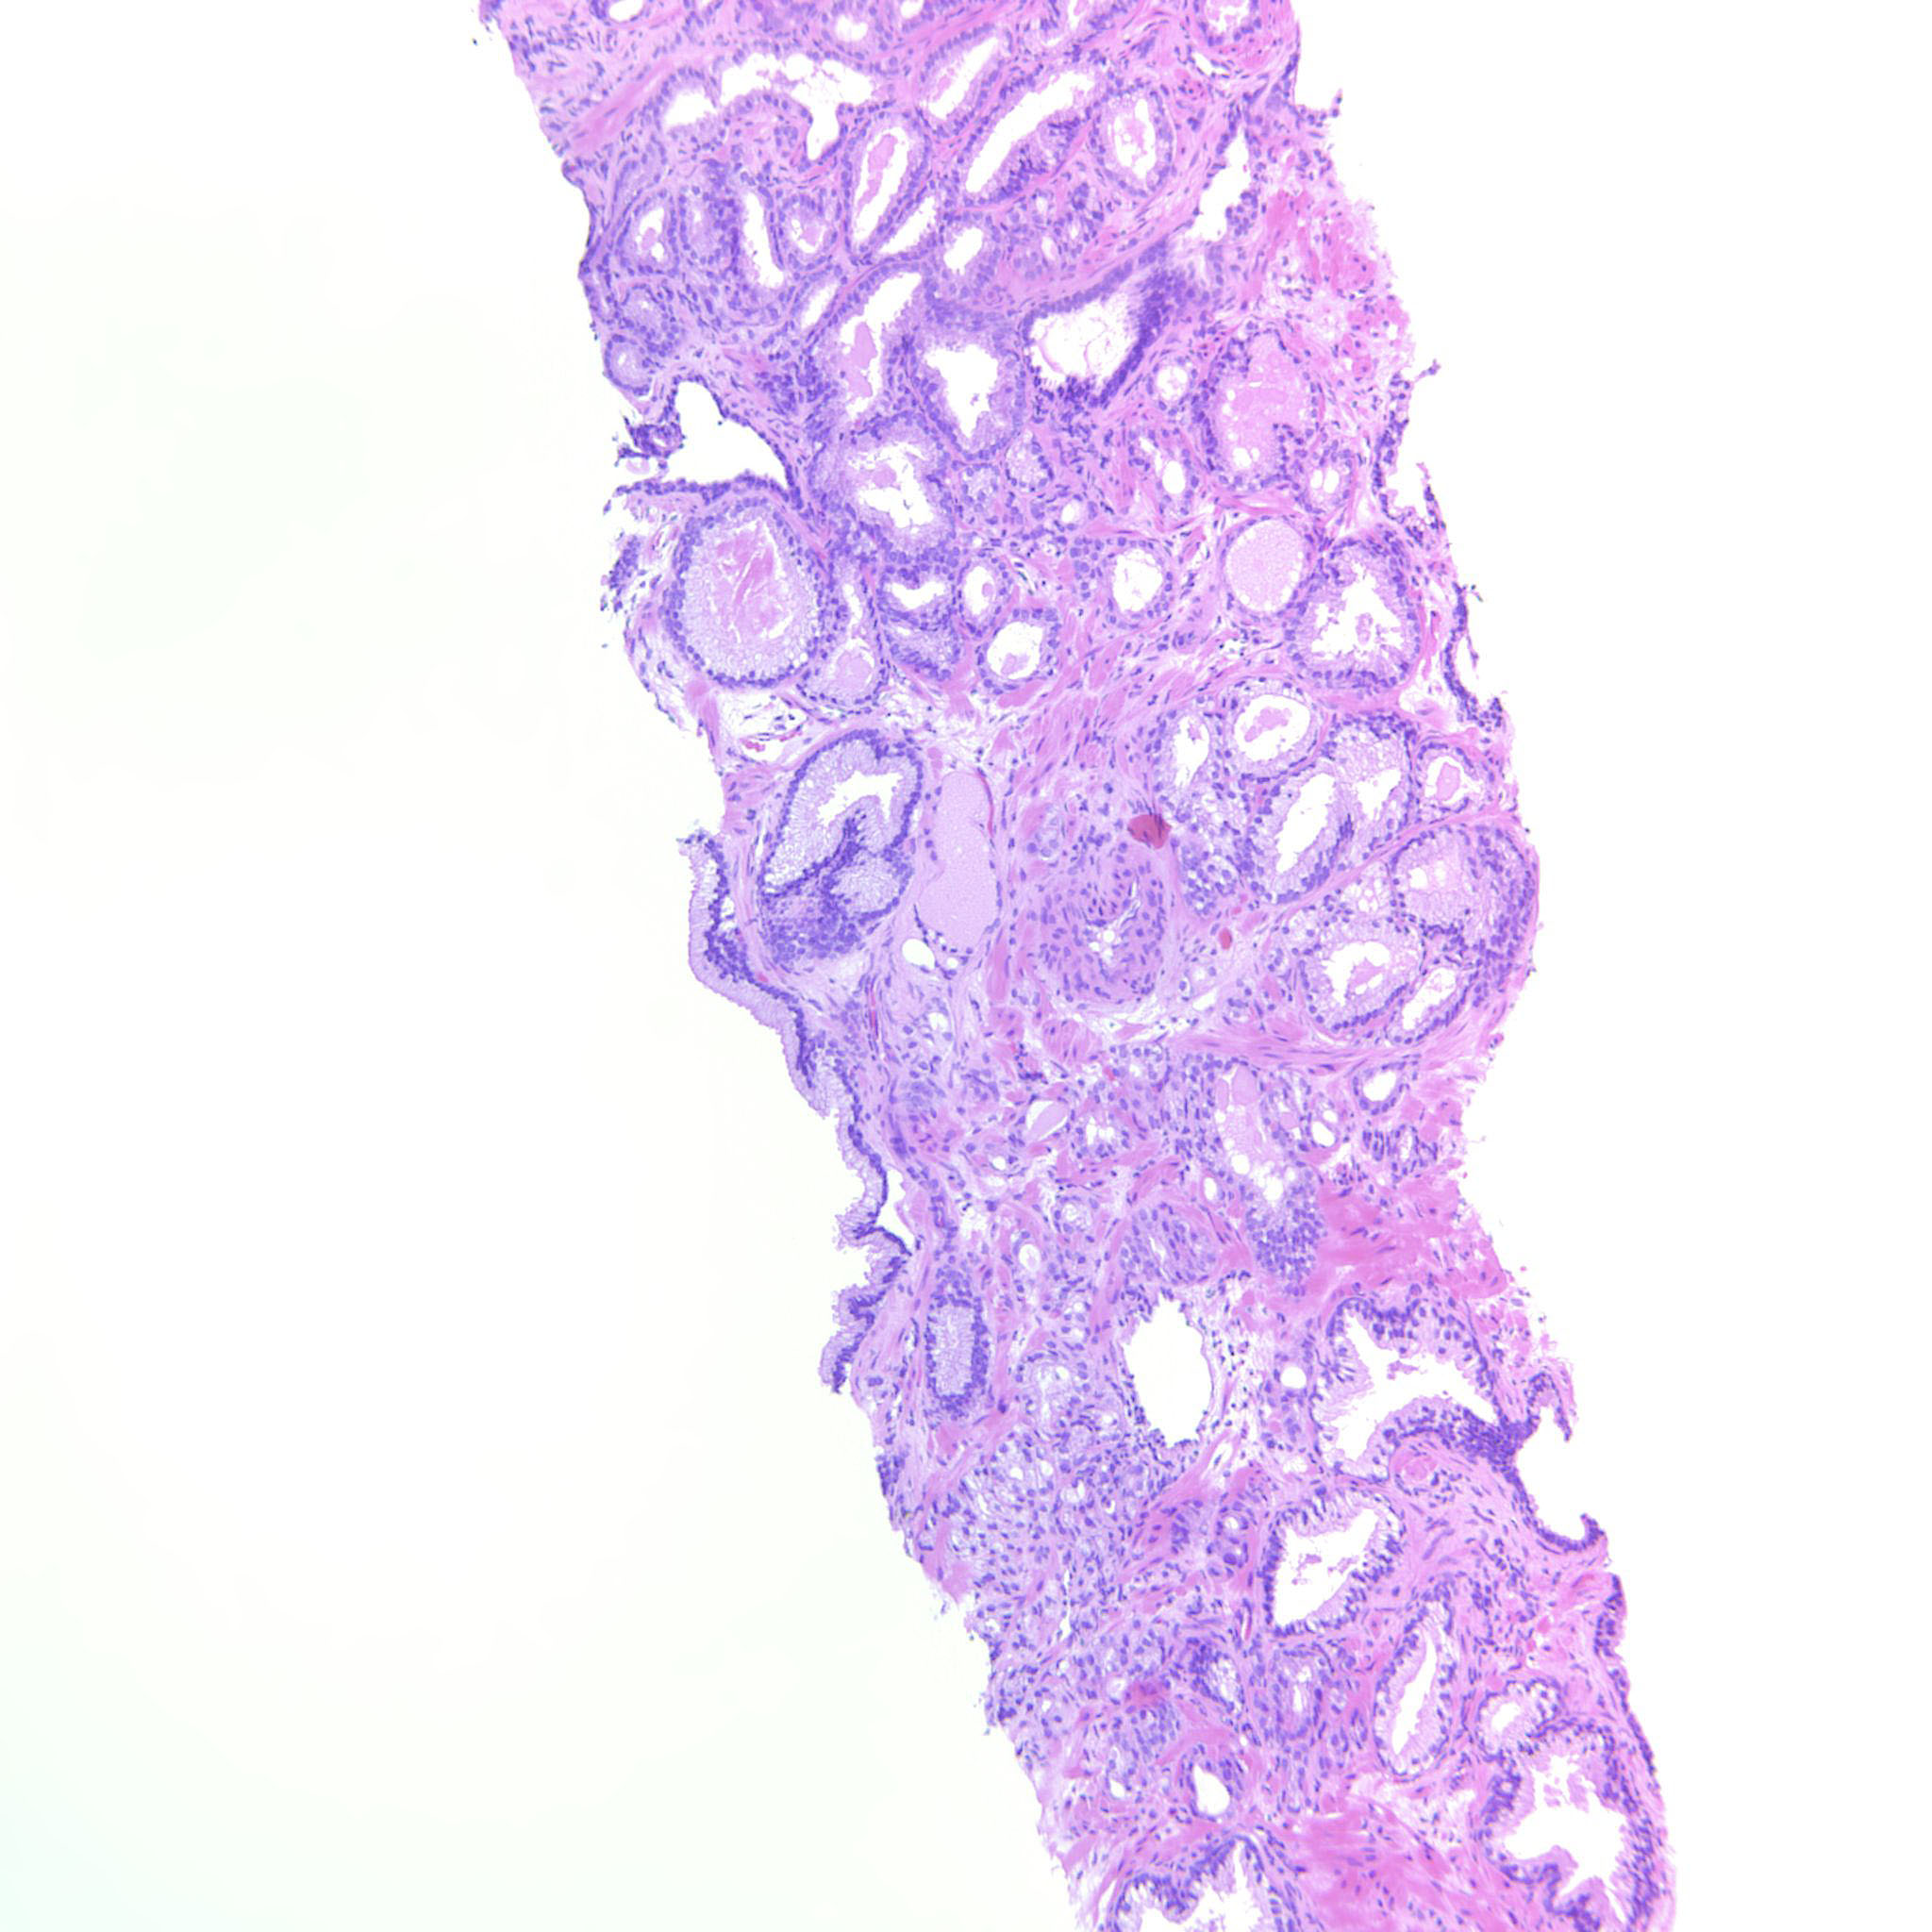

Prostate cancer grading

Case ID: 565